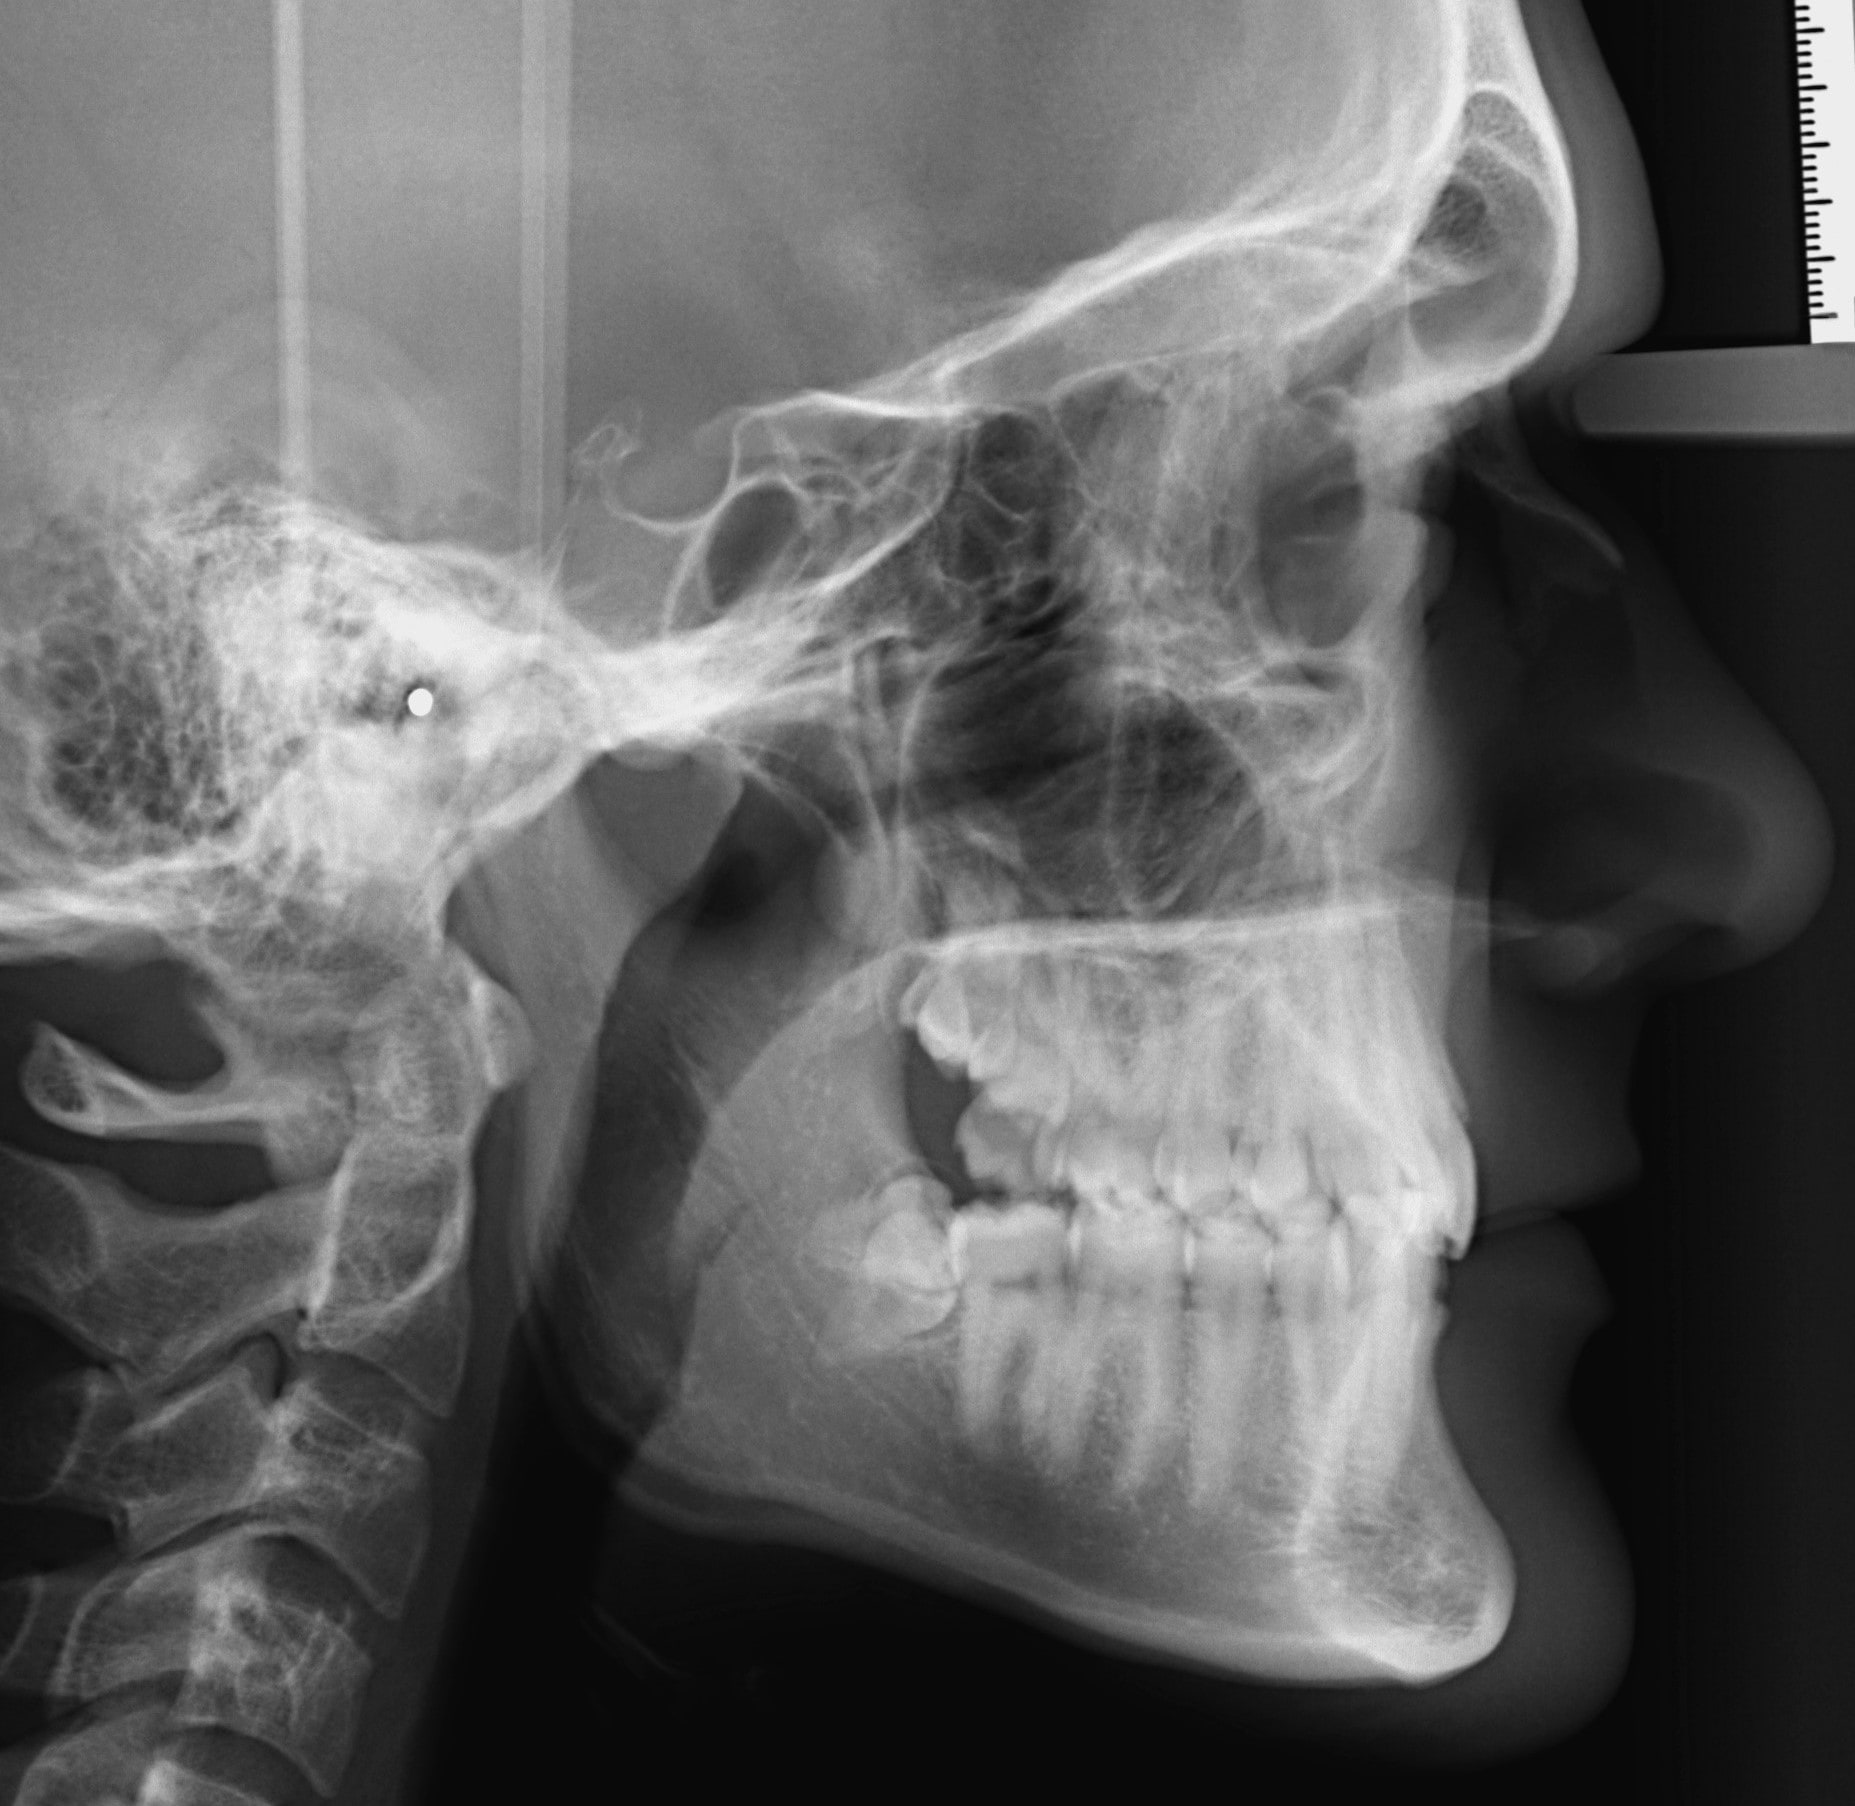

Oldalsó teleröntgen

Szinte 100%-ban fogszabályzási célból használt röntgenfelvétel. Gyakorlatilag egy oldalsó röntgenprofil. Látható rajta a metszőfogak tengelyállása, az állcsontok egymáshoz való viszonya a vertikális és szagittális síkban, elemezhetők a lágyrészek és a nyakcsigolyák. A nyakcsigolyák osztályozásával következtethetünk a páciens csontérettségi stádiumára is. A panoráma röntgennél is kisebb sugárterheléssel jár.

Nyakcsigolya érettségi besorolás (CVMS – Cervical Vertebral Maturation Staging)

Az oldalsó teleröntgenen látható nyakcsigolyák formájából, alakjából valamelyest következtetni lehet a gyermekek csontérettségi stádiumára. Számos készülék kizárólag adott stádiumban alkalmazható sikeresen. A besorolás 1-6-ig terjed. A kevésbé fejlett, differenciált nyaki csigolyákat a korábbi stádiumokba soroljuk (1-3. stádium), még az érettebbeket későbbiekbe (4-6. stádium). A CVMS is részét képezi annak a diagnosztikai összesítőnek, ami alapján eldöntöm, hogy melyik készüléket mikor alkalmazom. Például a bimaxilláris fogszabályozókat 3-4. stádiumban használom, a hyrax készülékeket a 2-3. stádiumban.